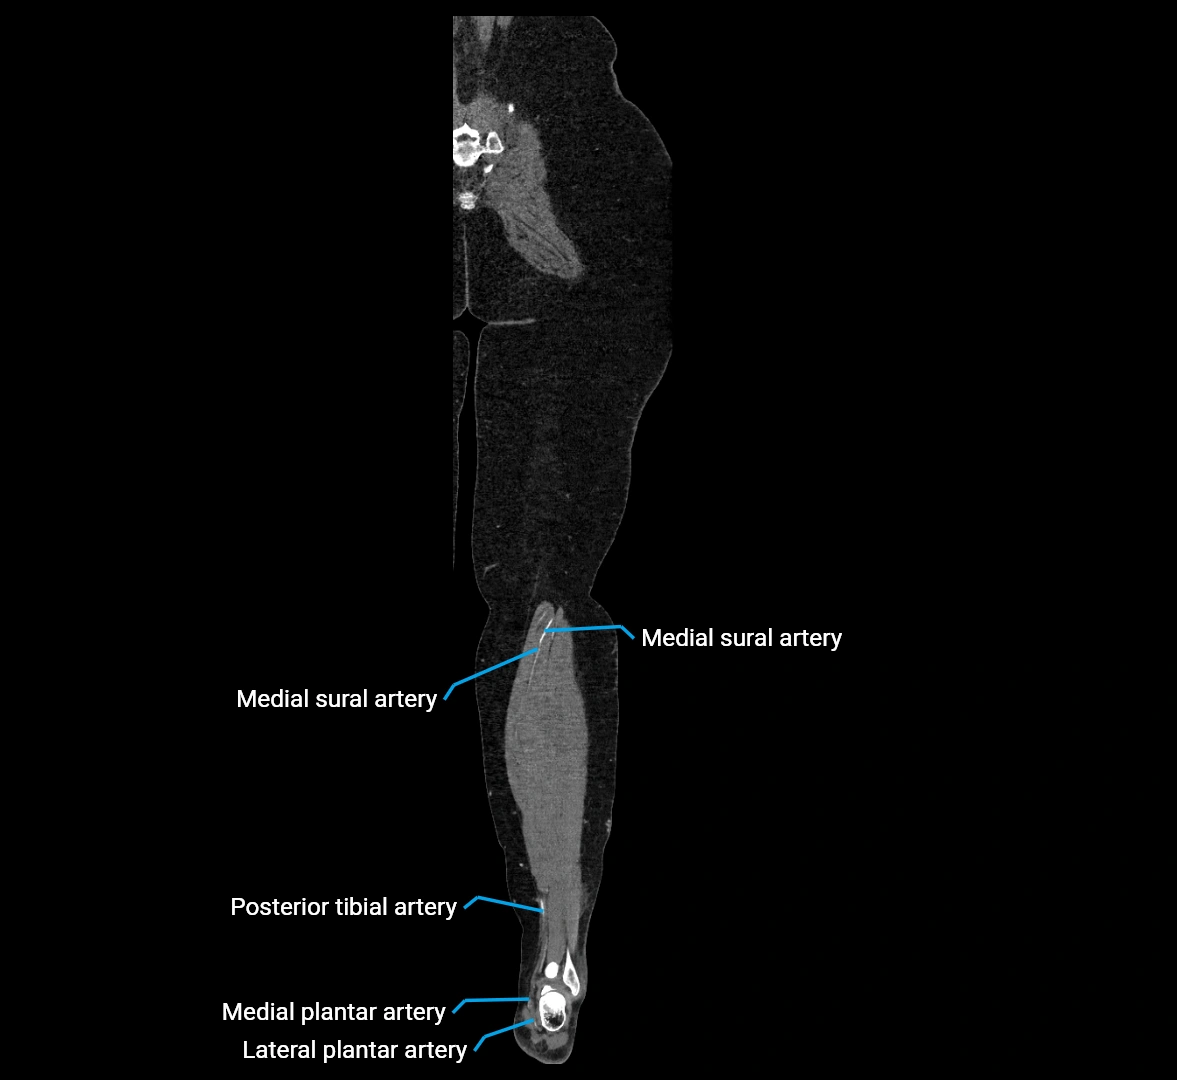

CT Appearance

Non-contrast CT:

• Appears as a tubular soft tissue structure anterior to vertebral bodies

• Calcified atherosclerotic plaques appear as hyperdense foci along the wall

• Useful for screening abdominal aortic aneurysm (AAA) size and mural calcification

Contrast-enhanced CT (CTA):

• Gold standard for abdominal aortic imaging

• Provides excellent detail of lumen, wall, aneurysm, thrombus, and branch vessels

• Multiplanar and 3D reconstructions help in aneurysm measurement, stent graft planning, and dissection evaluation

• Detects acute rupture, traumatic injury, or occlusion with high sensitivity